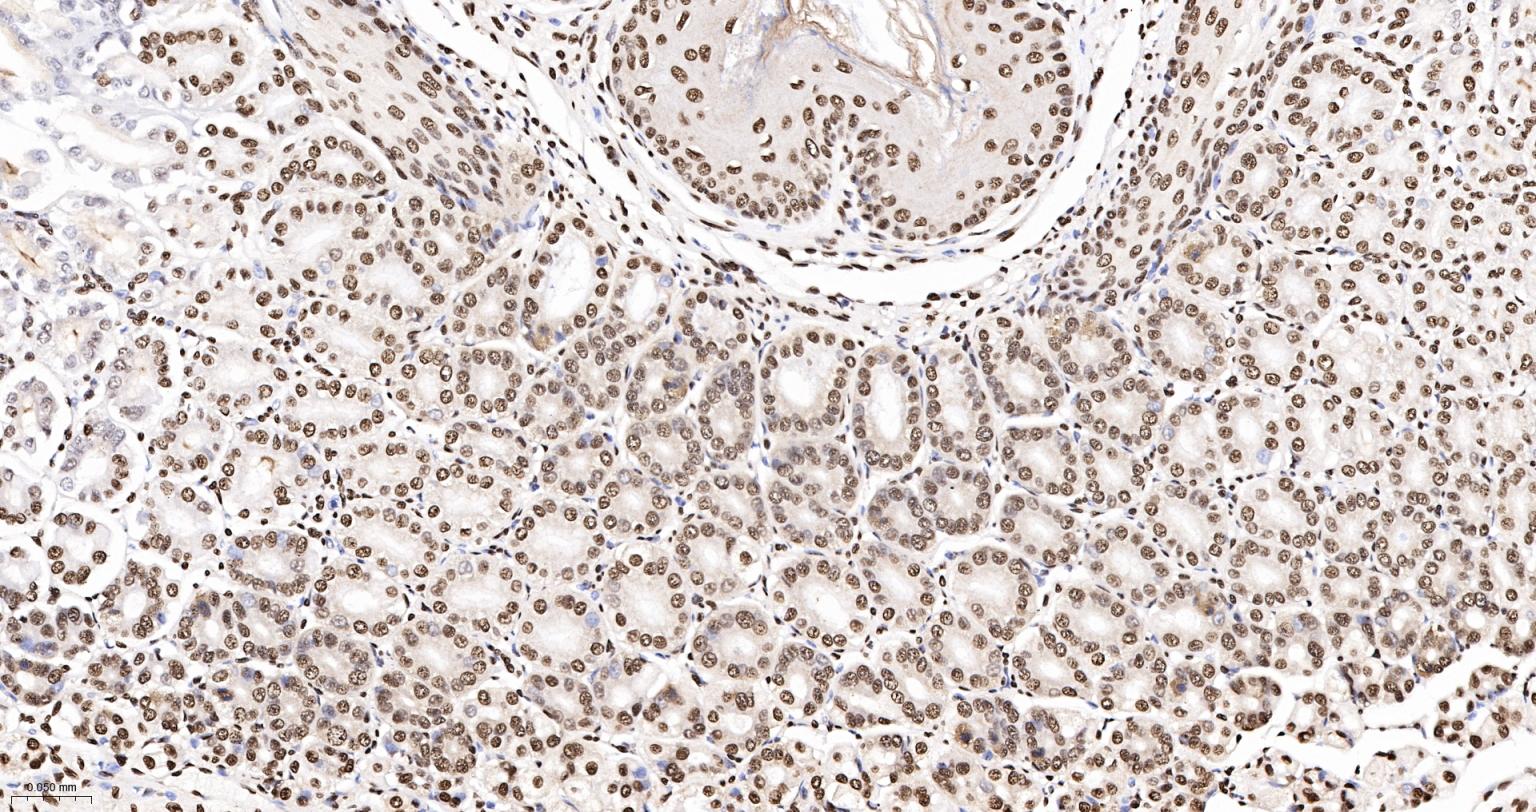

Paraformaldehyde-fixed, paraffin embedded Human Stomach; Antigen retrieval by boiling in sodium citrate buffer (pH6.0) for 15 min; The section was incubated with hnRNP K Monoclonal Antibody, Unconjugated (bsm-61246R) at 1:200 overnight at 4°C, followed by conjugation to the bs-0295G-HRP and DAB (C-0010) staining.